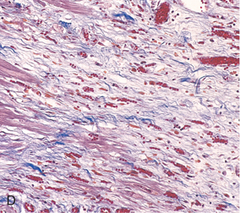

Necrotic Lesion